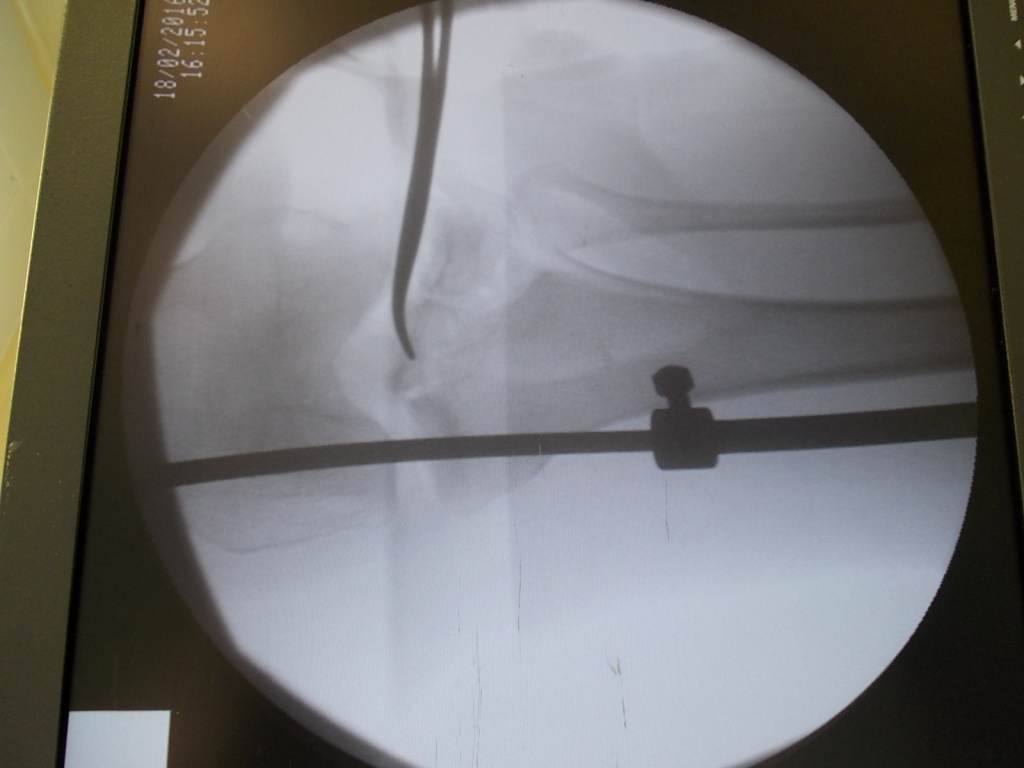

Использование материала Остеоматрикс при импрессионном оскольчатом переломе наружного мыщелка большеберцовой кости по типу Schatzker II

Использование материала Остеоматрикс при импрессионном оскольчатом переломе наружного мыщелка большеберцовой кости по типу Schatzker II.

Операция - открытая репозиция, остеосинтез большеберцовой кости опорной пластиной с костной ксенопластикой маетриалом "Остеоматрикс". На контрольных снимках в три и шесть месяцев имеется консолидация перелома, миграции фиксатора нет, имеется остеоинтеграция ксенопластического материала. Функция коленного сустава полная.